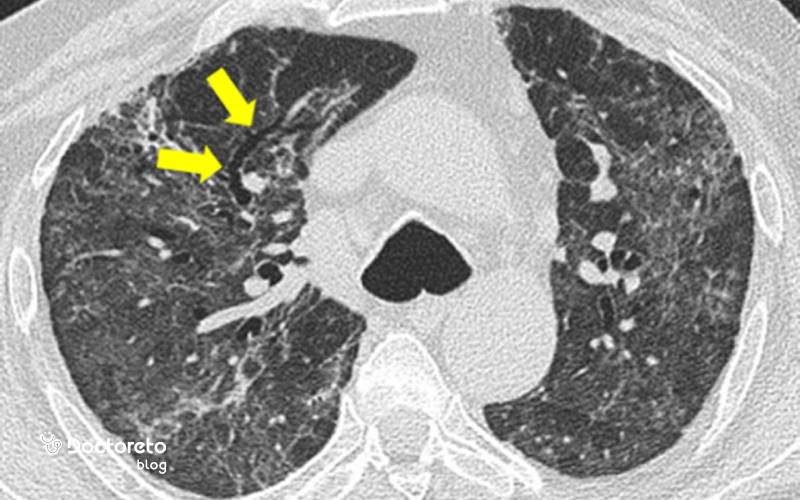

پزشک به الگوی تب، نوع سرفه، درد قفسه سینه و علائم حیاتی توجه میکند و در سمع به دنبال رال، کاهش صدا و علائم درگیری پلور میگردد و سپس رادیوگرافی قفسه سینه را برای تأیید ارتشاح و تعیین وسعت درخواست میکند. در موارد پیچیده یا عدم پاسخ به درمان اولیه، سیتیاسکن قفسه سینه به تعیین پاترن درگیری، وجود آبسه یا آمپیم کمک میکند. آزمایش خون برای سنجش شمارش سلولها و نشانگرهای التهاب و در موارد منتخب کشت خلط برای هدفمند کردن آنتیبیوتیک انجام میشود. سنجش اشباع اکسیژن و در موارد شدید گاز خون شریانی، شدت هیپوکسمی را مشخص میکند. آزمایشهای زیر نیز به تایید تشخیص پنومونی کمکمیکنند:

- سی تی اسکن قفسه سینه (chest CT-Scan)

پنومونی نکروزان فرم تهاجمی بیماری است که در آن بخشهایی از بافت ریه نکروزه میشوند و کاویتاسیون و آبسه شکل میگیرد و معمولاً با تب بالا، توکسیتی و خلط بدبو یا خونی همراه است. برای درمان این وضعیت آنتیبیوتیک تجویز میشود و نیاز است فرد در بیمارستان بررسی شود. تشخیص دقیق با سیتیاسکن کمک میکند وسعت درگیری و حضور حفرات را بسنجد و تصمیم درباره درناژ را هدایت کند. تأخیر در درمان خطر سپسیس و نارسایی تنفسی را بالا میبرد و دوره درمان اغلب طولانیتر از پنومونیهای معمولی است. برای بازگشت عملکرد ریع تغذیه کافی و توانبخشی لازم است.

پنومونی را میتوان بر اساس محل ابتلا، عامل بیماریزا و الگوی درگیری بافتی دستهبندی کرد تا انتخاب درمان هدفمند و پیشبینی سیر بیماری دقیقتر شود. پنومونی اکتسابی از جامعه معمولاً با عوامل متفاوتی نسبت به پنومونی اکتسابی از بیمارستان رخ میدهد و مقاومت دارویی در آن کمتر است. از سوی دیگر، پنومونی آتیپیک غالباً با سرفه خشک و تب ملایمتر همراه است و در تصویر رادیولوژیک الگوی بینابینی و پخش دارد که با الگوی لوبار در پنومونی پنوموکوکی تفاوت دارد. پنومونی نکروزان فرم شدیدتری است که میتواند با کاویتاسیون و آبسه همراه باشد و معمولاً نیاز به درمان تهاجمی و طولانیتر دارد.